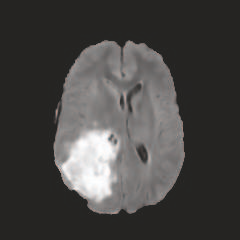

Multi-modal medical image completion has been extensively applied to alleviate the missing modality issue in a wealth of multi-modal diagnostic tasks. However, for most existing synthesis methods, their inferences of missing modalities can collapse into a deterministic mapping from the available ones, ignoring the uncertainties inherent in the cross-modal relationships. Here, we propose the Unified Multi-Modal Conditional Score-based Generative Model (UMM-CSGM) to take advantage of Score-based Generative Model (SGM) in modeling and stochastically sampling a target probability distribution, and further extend SGM to cross-modal conditional synthesis for various missing-modality configurations in a unified framework. Specifically, UMM-CSGM employs a novel multi-in multi-out Conditional Score Network (mm-CSN) to learn a comprehensive set of cross-modal conditional distributions via conditional diffusion and reverse generation in the complete modality space. In this way, the generation process can be accurately conditioned by all available information, and can fit all possible configurations of missing modalities in a single network. Experiments on BraTS19 dataset show that the UMM-CSGM can more reliably synthesize the heterogeneous enhancement and irregular area in tumor-induced lesions for any missing modalities.